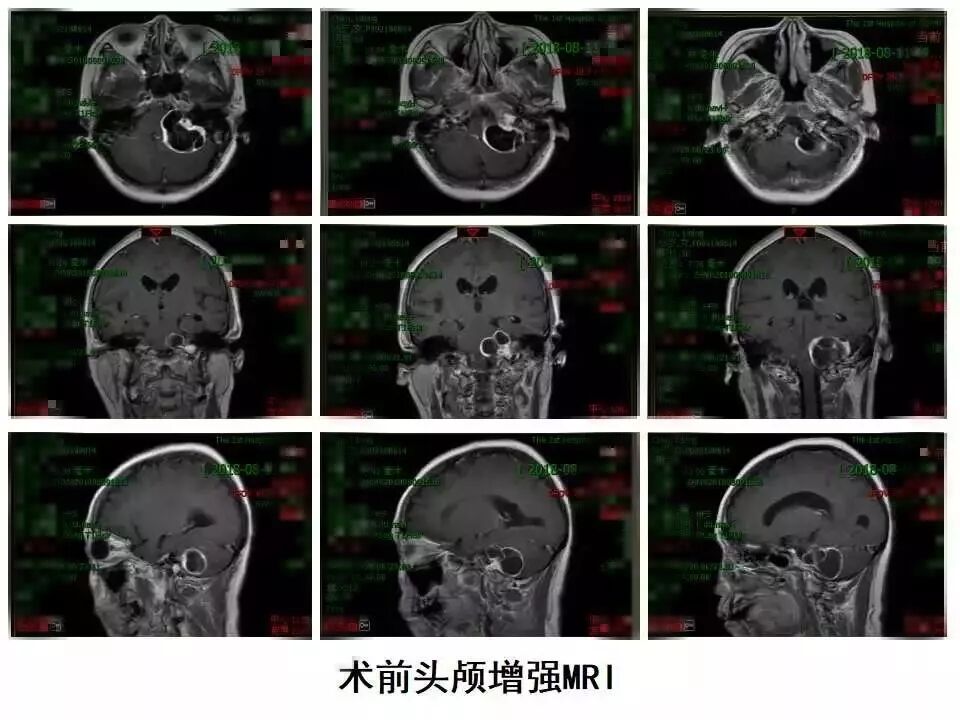

“双镜联合”切除A型颈静脉孔区神经鞘瘤